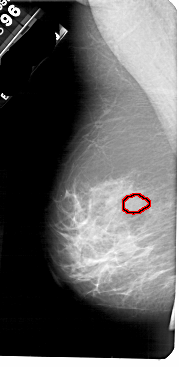

FILE: A_1838_1.LEFT_MLO.OVERLAY

TOTAL_ABNORMALITIES 1

ABNORMALITY 1

LESION_TYPE MASS SHAPE LOBULATED MARGINS OBSCURED

ASSESSMENT 3

SUBTLETY 4

PATHOLOGY BENIGN

TOTAL_OUTLINES 1

BOUNDARY

LEFT_MLO LINES 5491 PIXELS_PER_LINE 2671 BITS_PER_PIXEL 12 RESOLUTION 43.5 OVERLAY